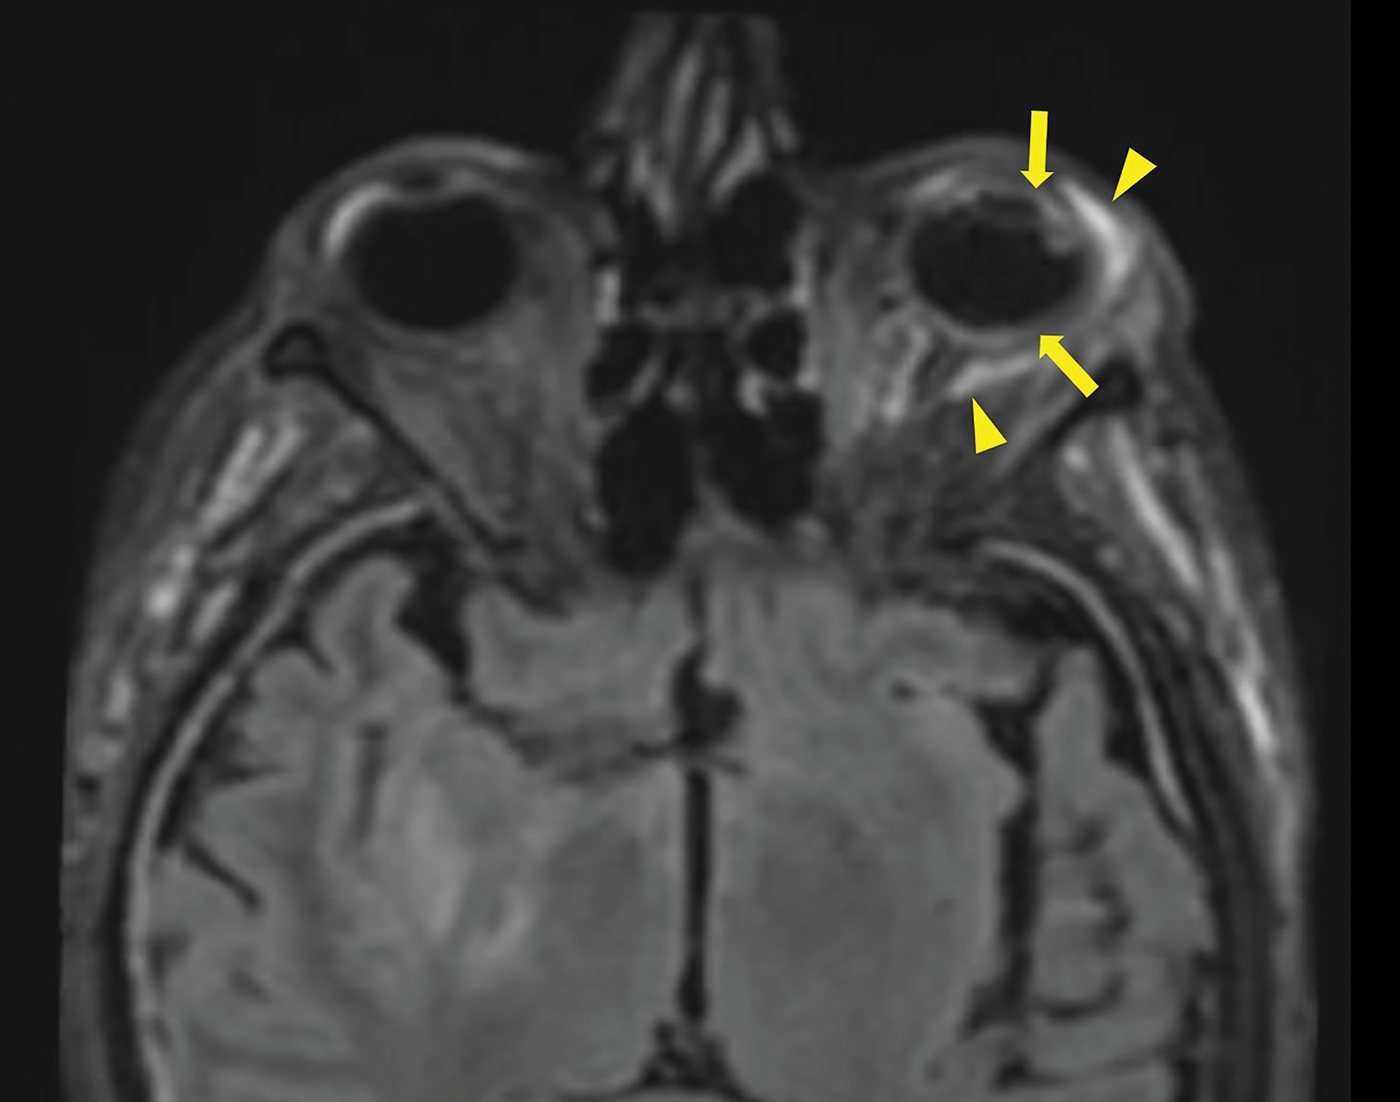

Figure 2

3D FLAIR Sequence with Fat saturation post contrast injection showing a pre‑septal and a perioptic hypersignal (arrowheads), a increase signal of the choroid and of the ciliary body. Also note the thickened dura mater in relation to the meningitis.